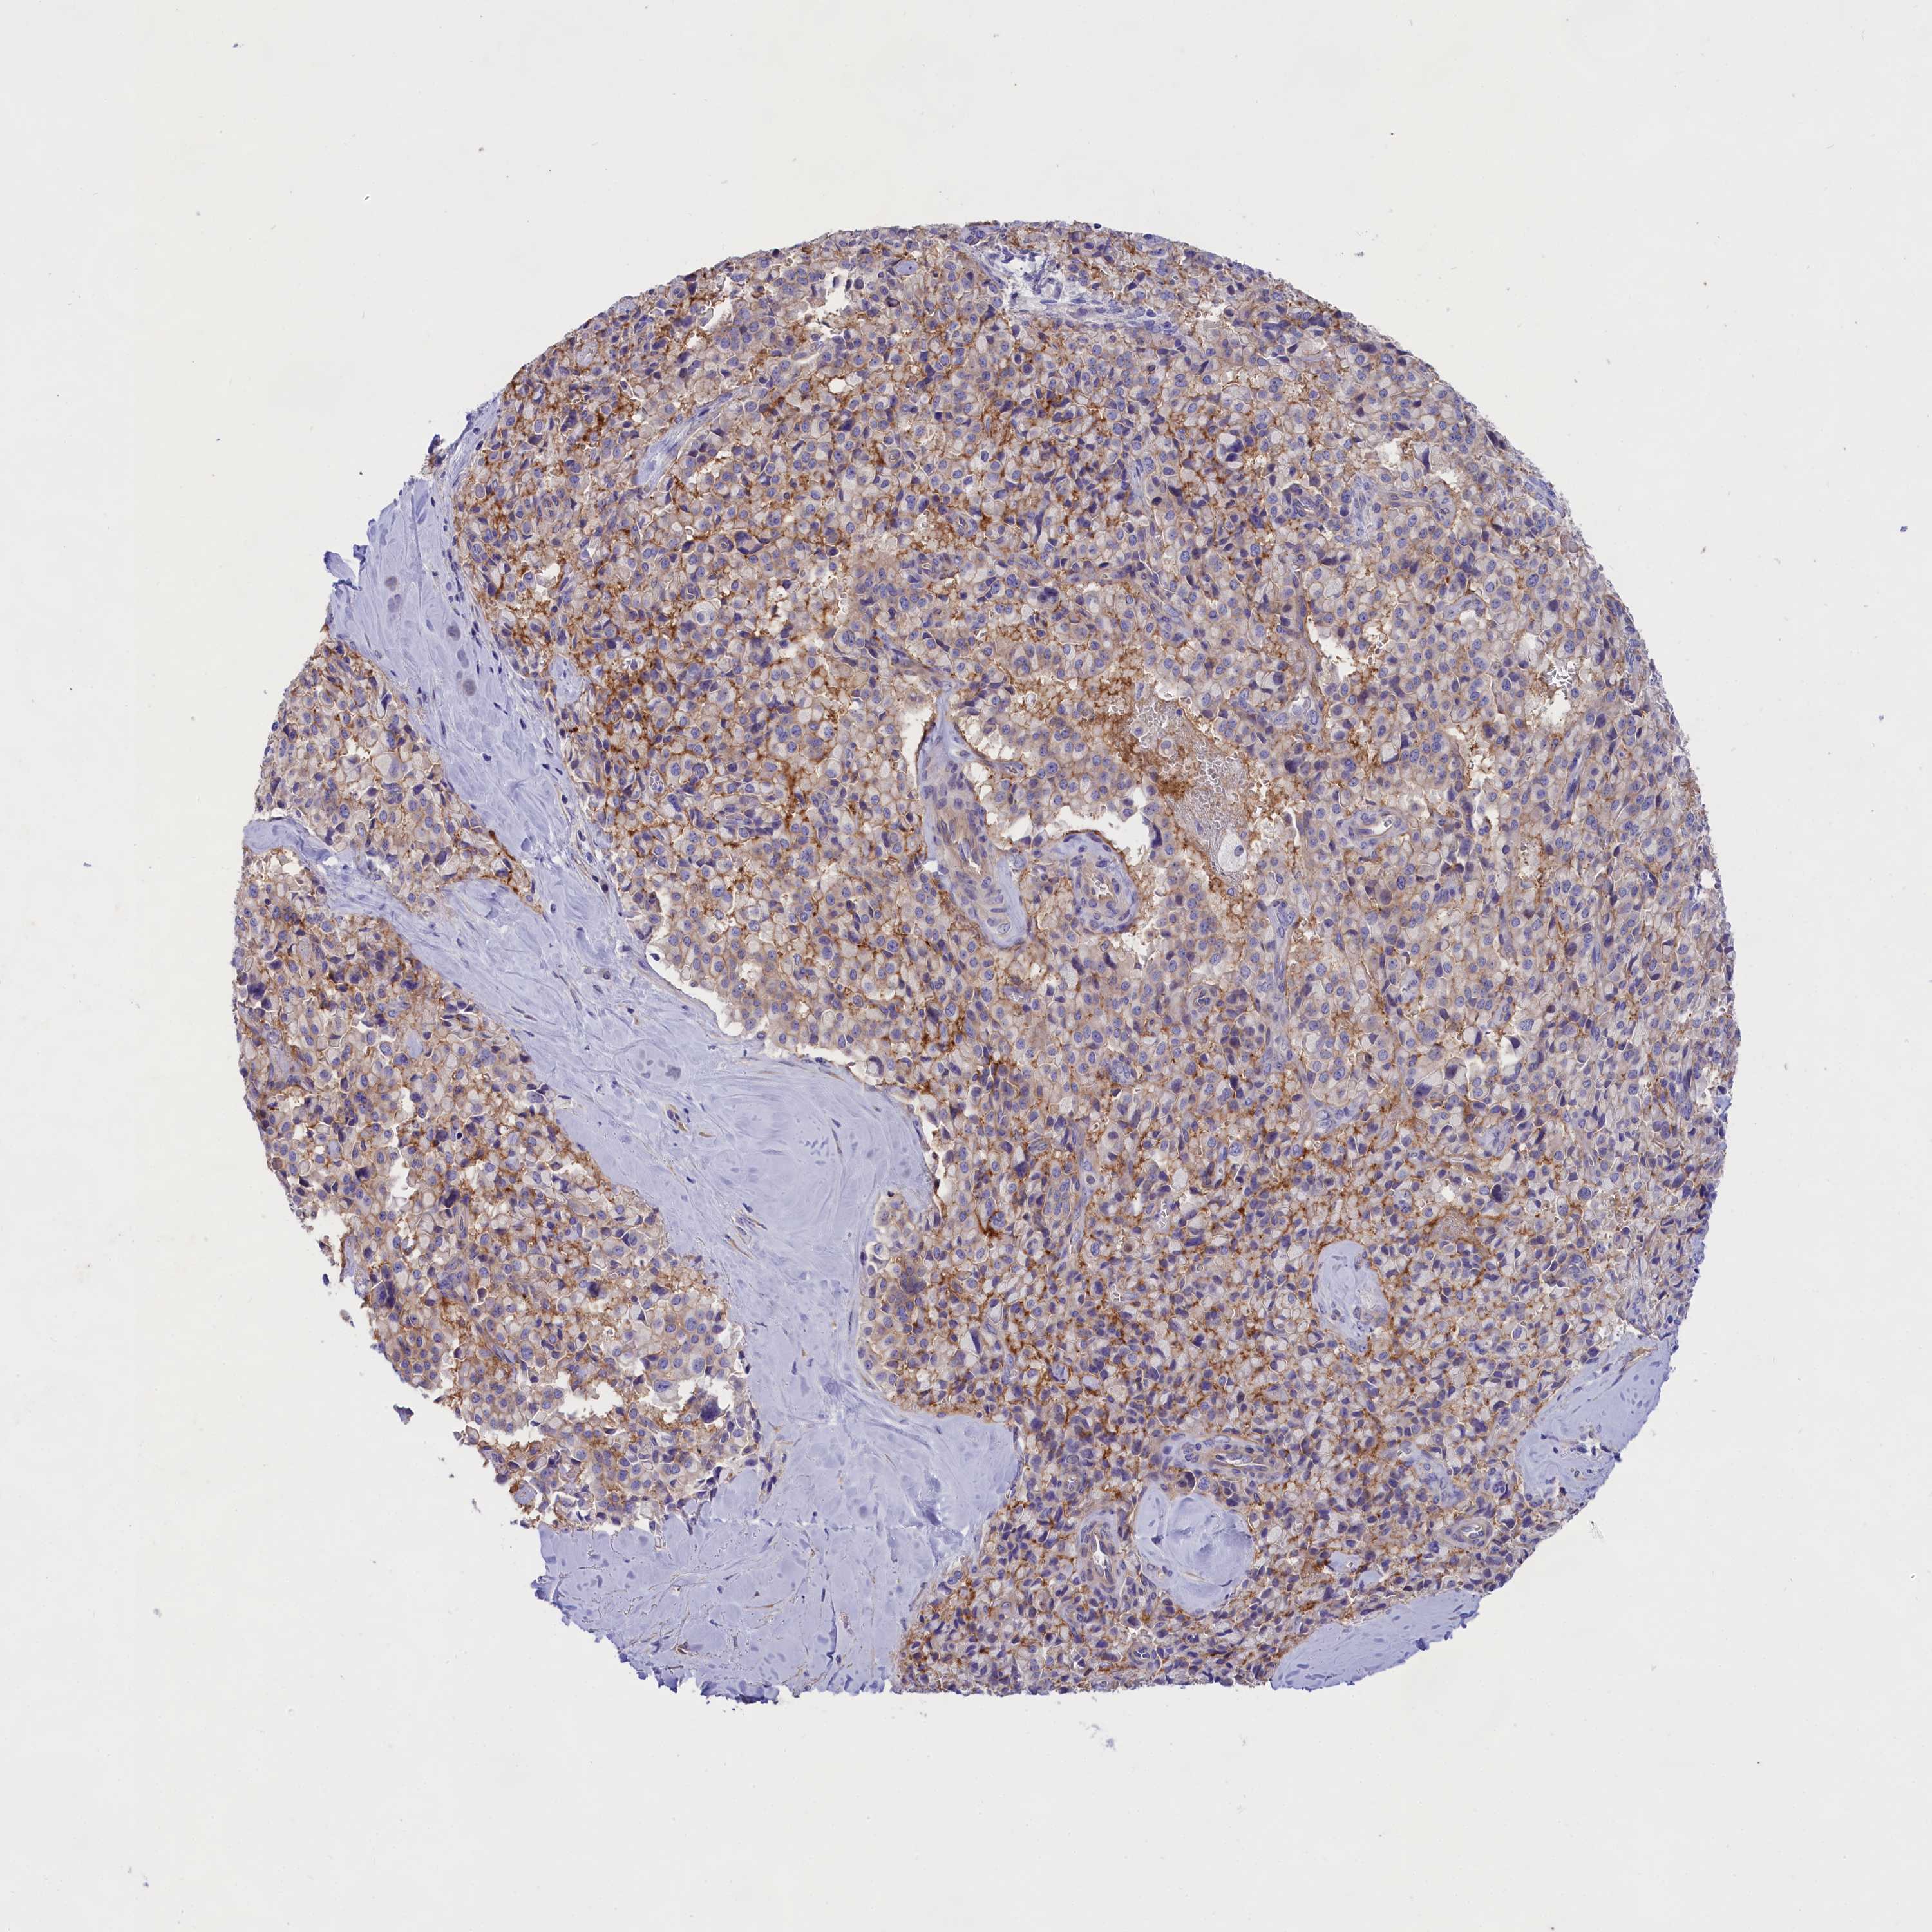

PANCREATIC CANCER - Protein expressioni

A mouse-over function shows sample information and annotation data. Click on an image to view it in a full screen mode. Samples can be filtered based on level of antibody staining by selecting one or several of the following categories: high, medium, low and not detected. The assay and annotation is described here.

Note that samples used for immunohistochemistry by the Human Protein Atlas do not correspond to samples in the TCGA dataset.

Antibody stainingi

Antibody staining in the annotated cell types in the current human tissue is reported as not detected, low, medium, or high, based on conventional immunohistochemistry profiling in selected tissues. This score is based on the combination of the staining intensity and fraction of stained cells.

Each image is clickable and will lead to virtual microscopy that enables deeper exploration of all samples and also displays staining intensity scores, fraction scores and subcellular localization as well as patient and tissue information for each sample.

Antibody HPA041231

Antibody HPA059883

Antibody CAB005016

Staining

High

Medium

Low

Not detected

Intensity

Strong

Moderate

Weak

Negative

Quantity

>75%

75%-25%

<25%

None

Location

Nuclear

Cytoplasmic/membranous

Cytoplasmic/membranous,nuclear

Adenocarcinoma, NOS

Adenocarcinoma, metastatic, NOS